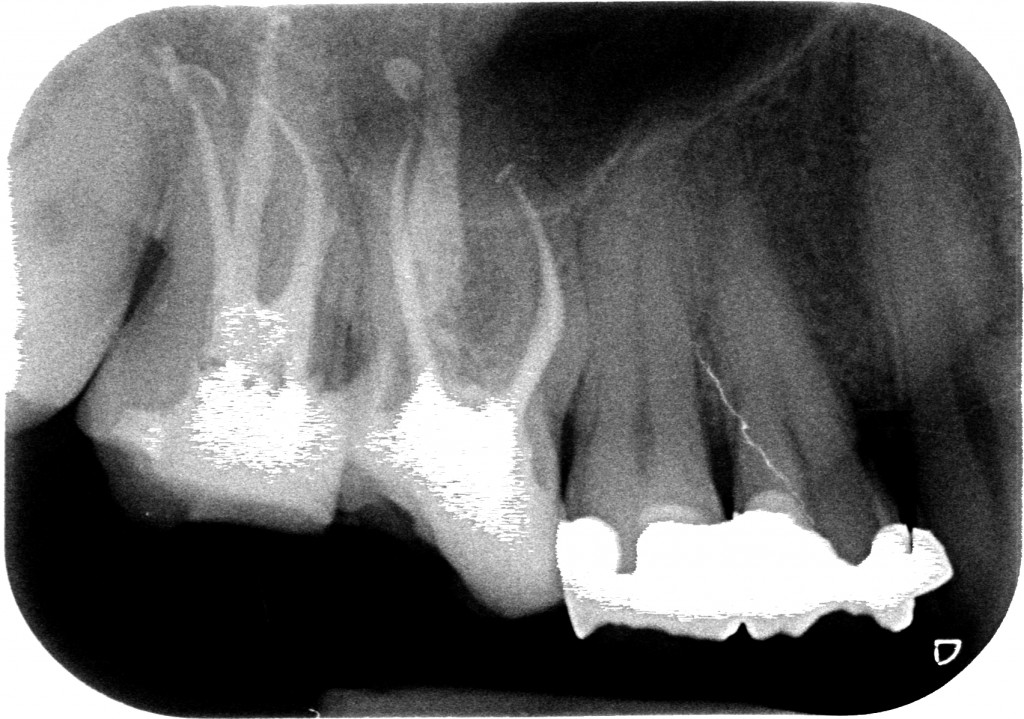

Questo sabato non ha fatto eccezione e mi sono trovato in agenda un ritrattamento di un 1.7 che già dalla radiografia preoperatoria mi ha fatto drizzare le antenne.?

Vedi quel canale mesio-vestibolare? Per esperienza so che quando il dentista che ci ha preceduto è in grado di arrivare in apice su due canali e sul terzo si perde prima della curva di una radice possono essere capitate solo due cose, perchè escludo che sia semplicemente un incapace che non sa fare l’endodonzia:

Ed ecco la rx.

A questo punto il paziente non si preoccupa perchè si è verificato esattamente quello che avevi previsto e capisce che la situazione è difficile ma sai cosa stai facendo.